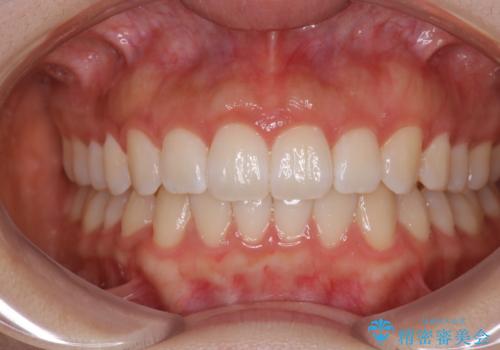

前歯のがたつきをインビザラインで目立たない矯正

- 上下の前歯のがたつきを主訴に来院されました。

マウスピースでの矯正を希望されたので、インビザラインで矯正治療を行うこととしました。

インビザラインではシュミレーションによりどのように歯が動くかを確認して矯正することができるので、患者様も安心して矯正をすることができました。